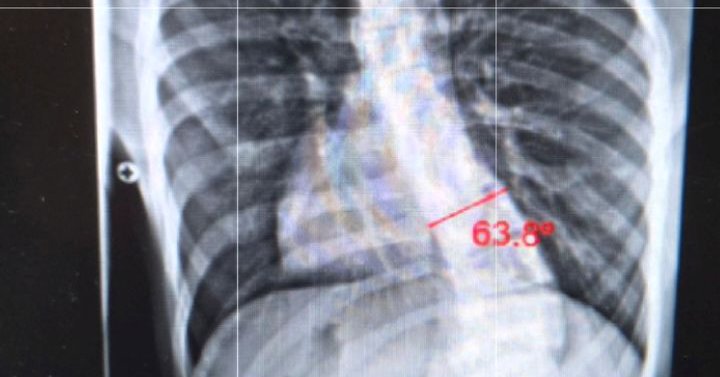

gofund.me/3d429a3a2 We’re going through a difficult medical situation and could really use some help. Any support or even sharing this would mean so much—thank you! #scoliosis #donate #money #gofund #give

Donate to Give My Son a Chance at a Pain-Free Future, organized by Nate G Gonzalez

My son was diagnosed with scoliosis, a condition that is causing a severe c… Nate G Gonzalez needs your support for Give My Son a Chance at a Pain-Free Future